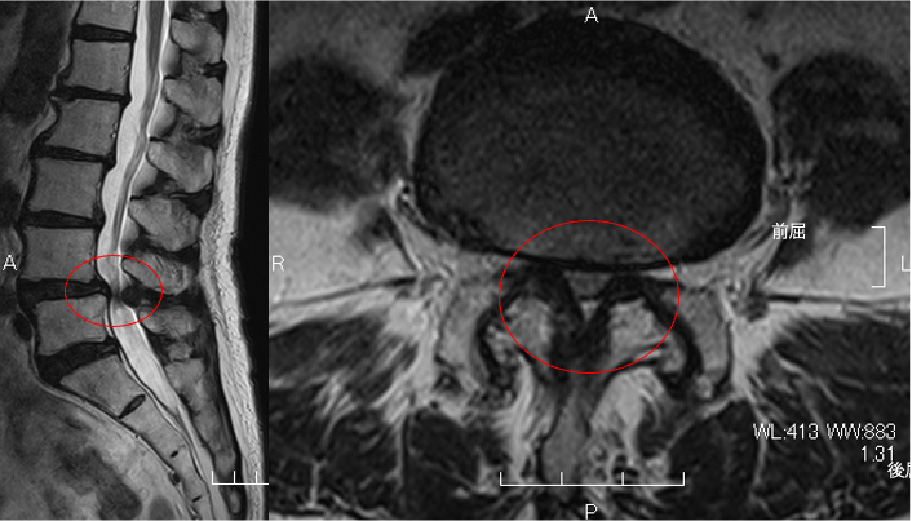

術前MRI:大きなヘルニア

(左図の矢印、右図の丸印)

を認め神経を強く圧迫しています